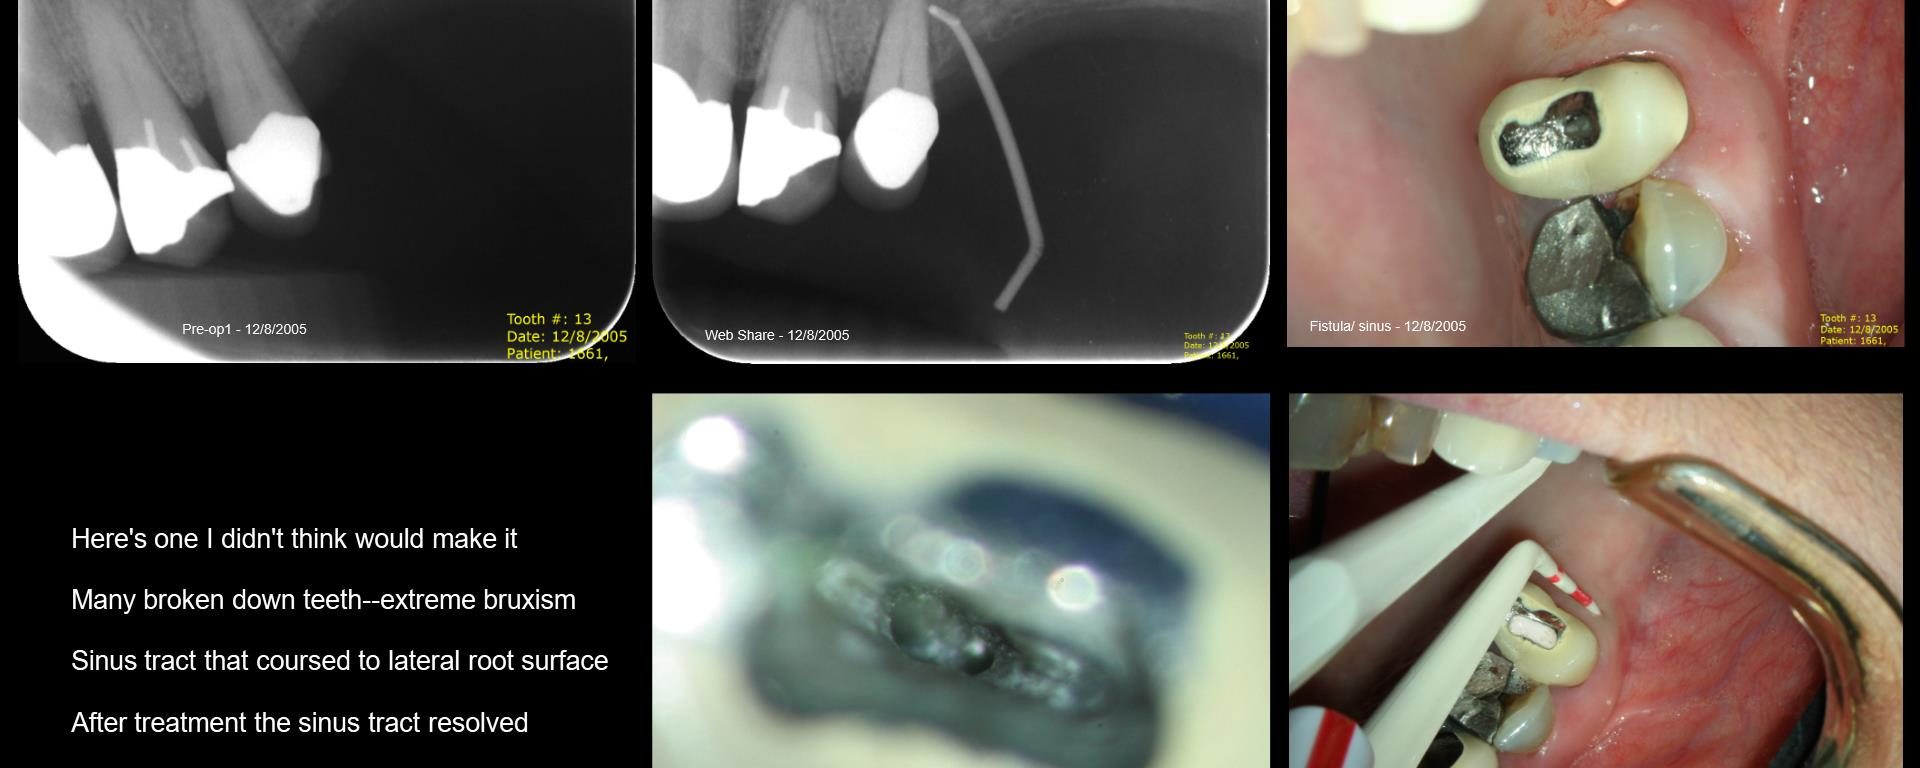

13 years on a tooth which shouldn’t have made it

July 31, 2018 2 comments

Gary CarrJuly 31, 2018 2 comments